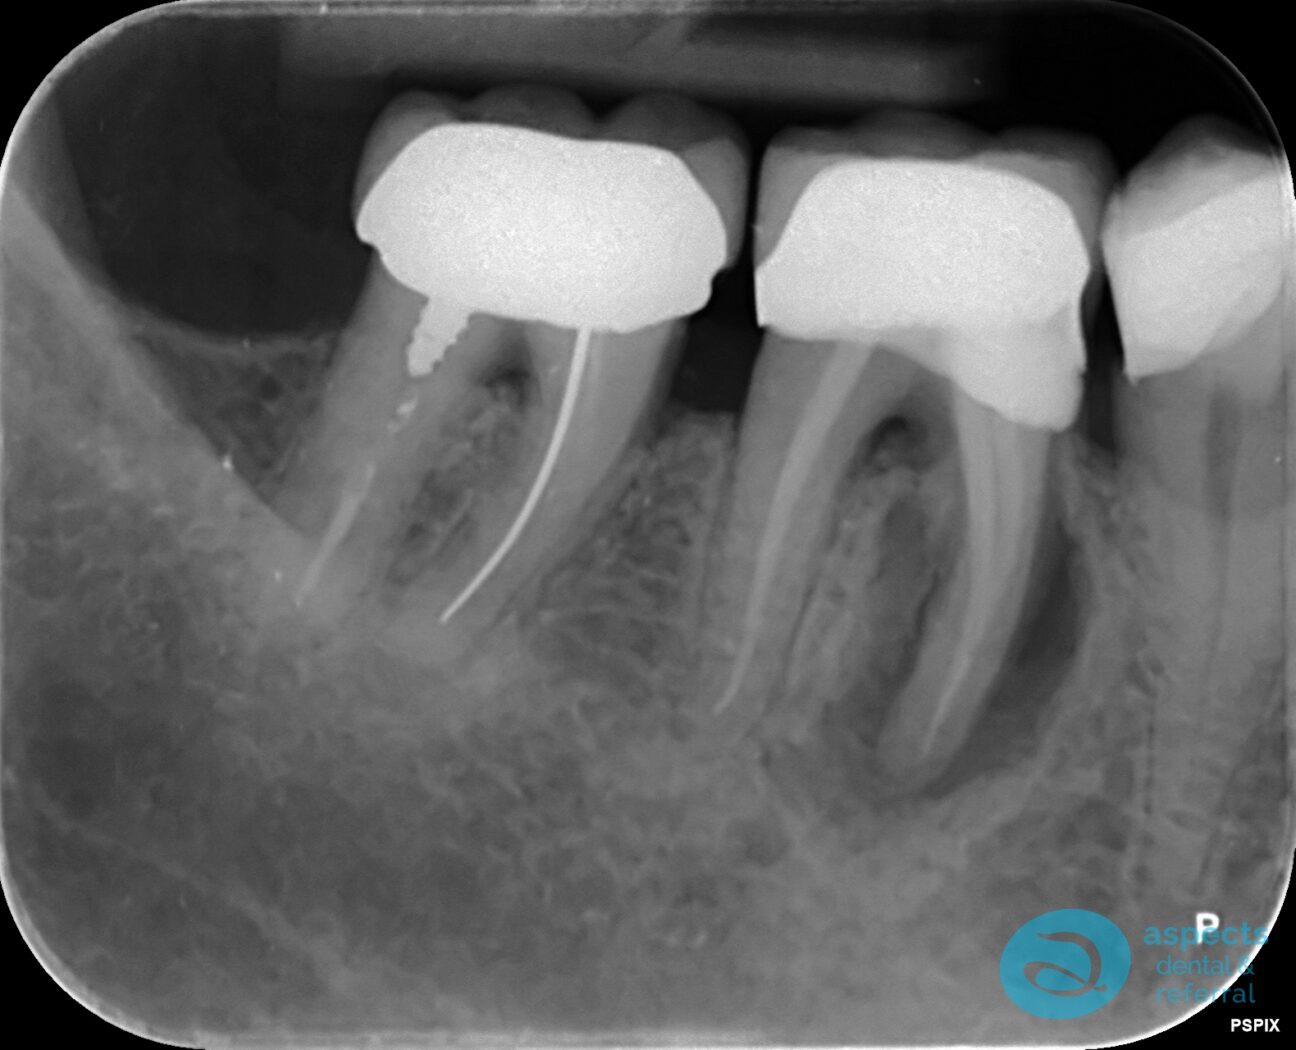

Our Dental Patient presented with a previously Root Canal Treated Molar that was failing due to persistent infection and structural compromise. After clinical and radiographic assessment, the tooth was deemed non-restorable.

Before Tooth Extraction & Dental Implant Xray